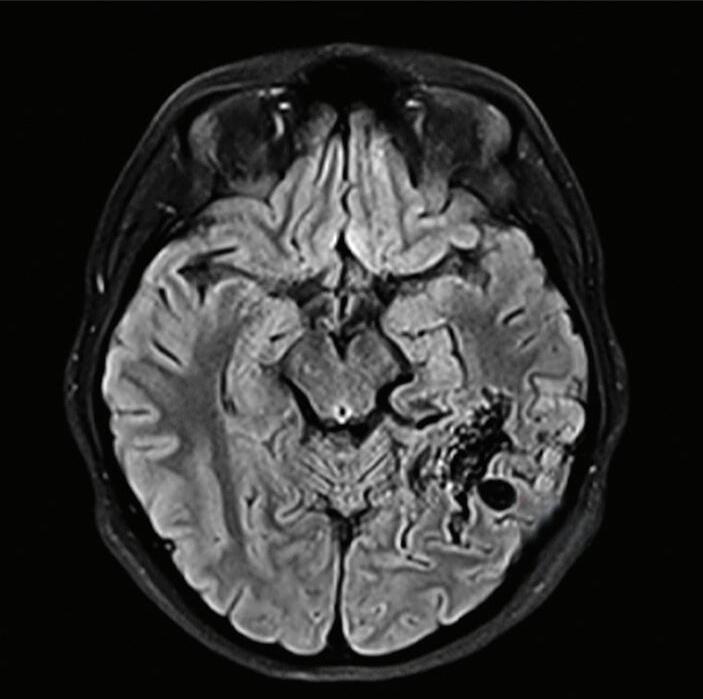

Fig. 1-20. RNM T1 com contraste em cortes (a) axial e (b) sagital e (c) FLAIR axial, demonstrando MAV do giro fusiforme esquerdo com presença do aneurisma pós-nidal (setas azuis). Angiografia pré-operatória em (d) AP e (e) em perfil mostrando a MAV anteriormente descrita, nutrida por ramos da artéria cerebral média e posterior esquerda, com drenagem superficial para o seio transverso e sigmoide ipsilateral e aneurisma pós-nidal venoso (setas azuis). (f) Visão intraoperatória do aneurisma pós-nidal (seta azul).